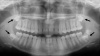

There isn’t necessarily a universal answer since the timing for wisdom teeth removal is dependent on individual circumstances. However, timing can easily be determined with an oral examination and review of X-rays.

What age do you get your wisdom teeth?

The answer to this question varies. Wisdom teeth are the final adult teeth to develop, so they usually emerge between the ages of 17 and 25. However, these teeth begin to develop around age 5. X-rays allow dentists to monitor the development of these final molars in relation to the rest of your oral structures to determine whether your wisdom teeth will become problematic. Most people get their wisdom teeth removed between the ages of 15 and 20, ideally before problems arise.